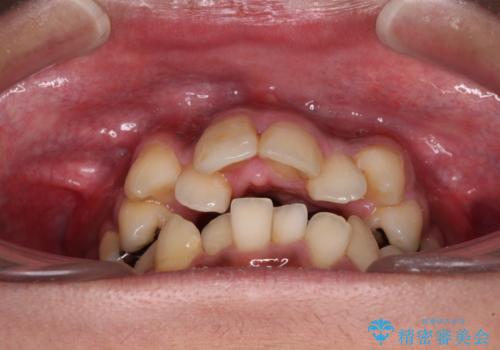

八重歯と開咬 ワイヤー装置での抜歯矯正

- 前歯のデコボコと八重歯、開咬を気にして来院された患者様です。

骨格的に下顎骨が上顎骨に対して後退位であったため、上顎の左右第一小臼歯を抜歯し、デコボコを改善するとともに開咬を改善していくこととしました。

舌の突出癖により開咬となっていたため、突出癖改善のためのトレーニングをしっかりと行っていただき、予定の期間で無事に治療を終えることができました。